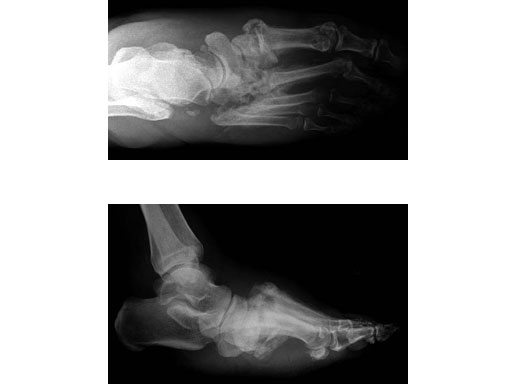

Case 1: 47-year-old female

Case provided by Andrew K Sands, New York, USA

Charcot foot treated with MFB and X-plate